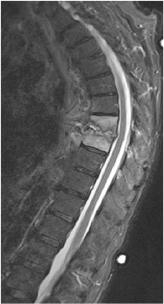

Uma paciente de 45 anos de idade com história de infecção urinária de repetição foi admitida na emergência de um hospital com dor dorsal lancinante. O exame neurológico é normal e a ressonância magnética é mostrada a seguir.

O diagnóstico mais provável para esse caso é: